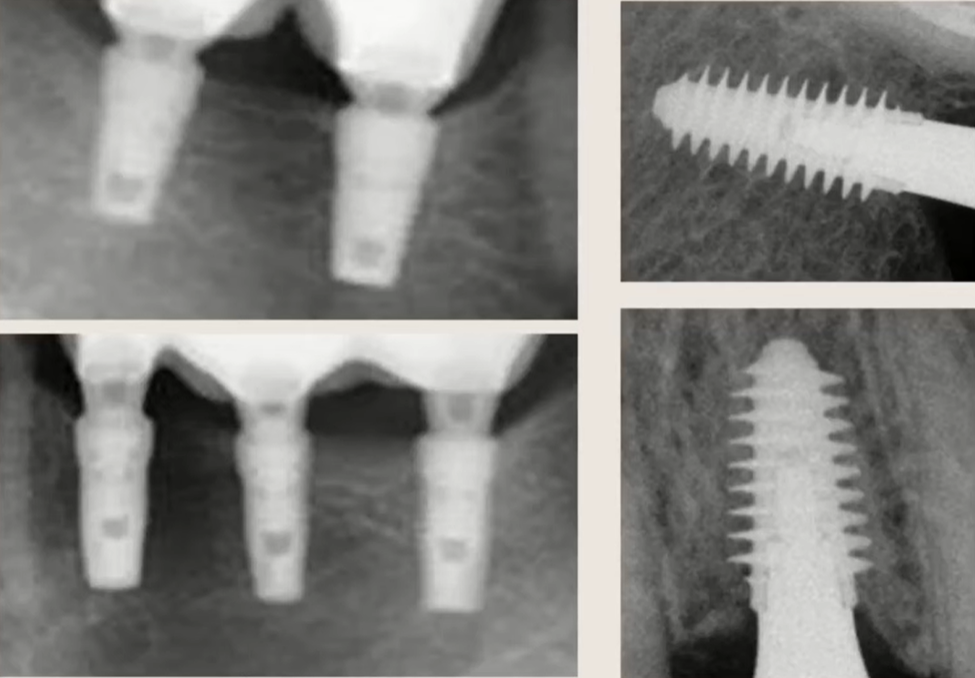

The implant architecture in the model was complex, including three fences (support ribs) to simulate real structural elements at the bone-implant interface.

The researchers created a 3D model of the implant in CATIA and performed the simulation in ANSYS:

- implant length:8 mm

- diameter:4.5 mm

- three “fences”: two 2 mm, one 1.5 mm

- bone: 1 mm cortical layer + trabecular bone

- 81,000 nodes, 27,000 mesh elements

The model was the same for all materials to eliminate the influence of geometry.